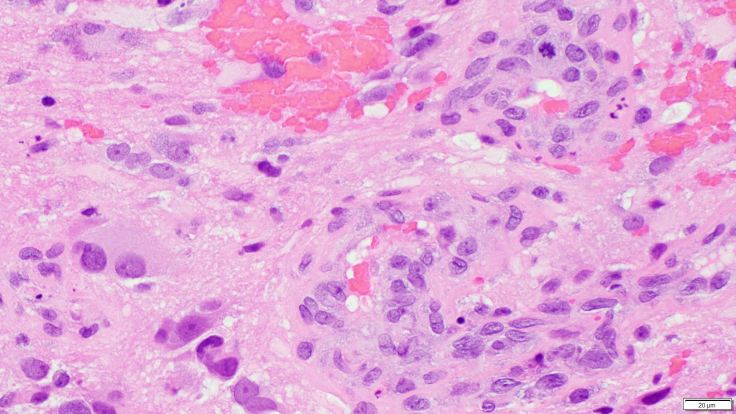

Glioblastomas are high grade astrocytomas that often exhibit microvascular proliferation, characterized by atypical hypertrophic and hyperplastic endothelial cells. A mitotic figure within a proliferating endothelial cell is present in the top right corner of the image.